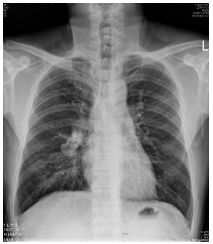

7.CC: cough for one year and back pain